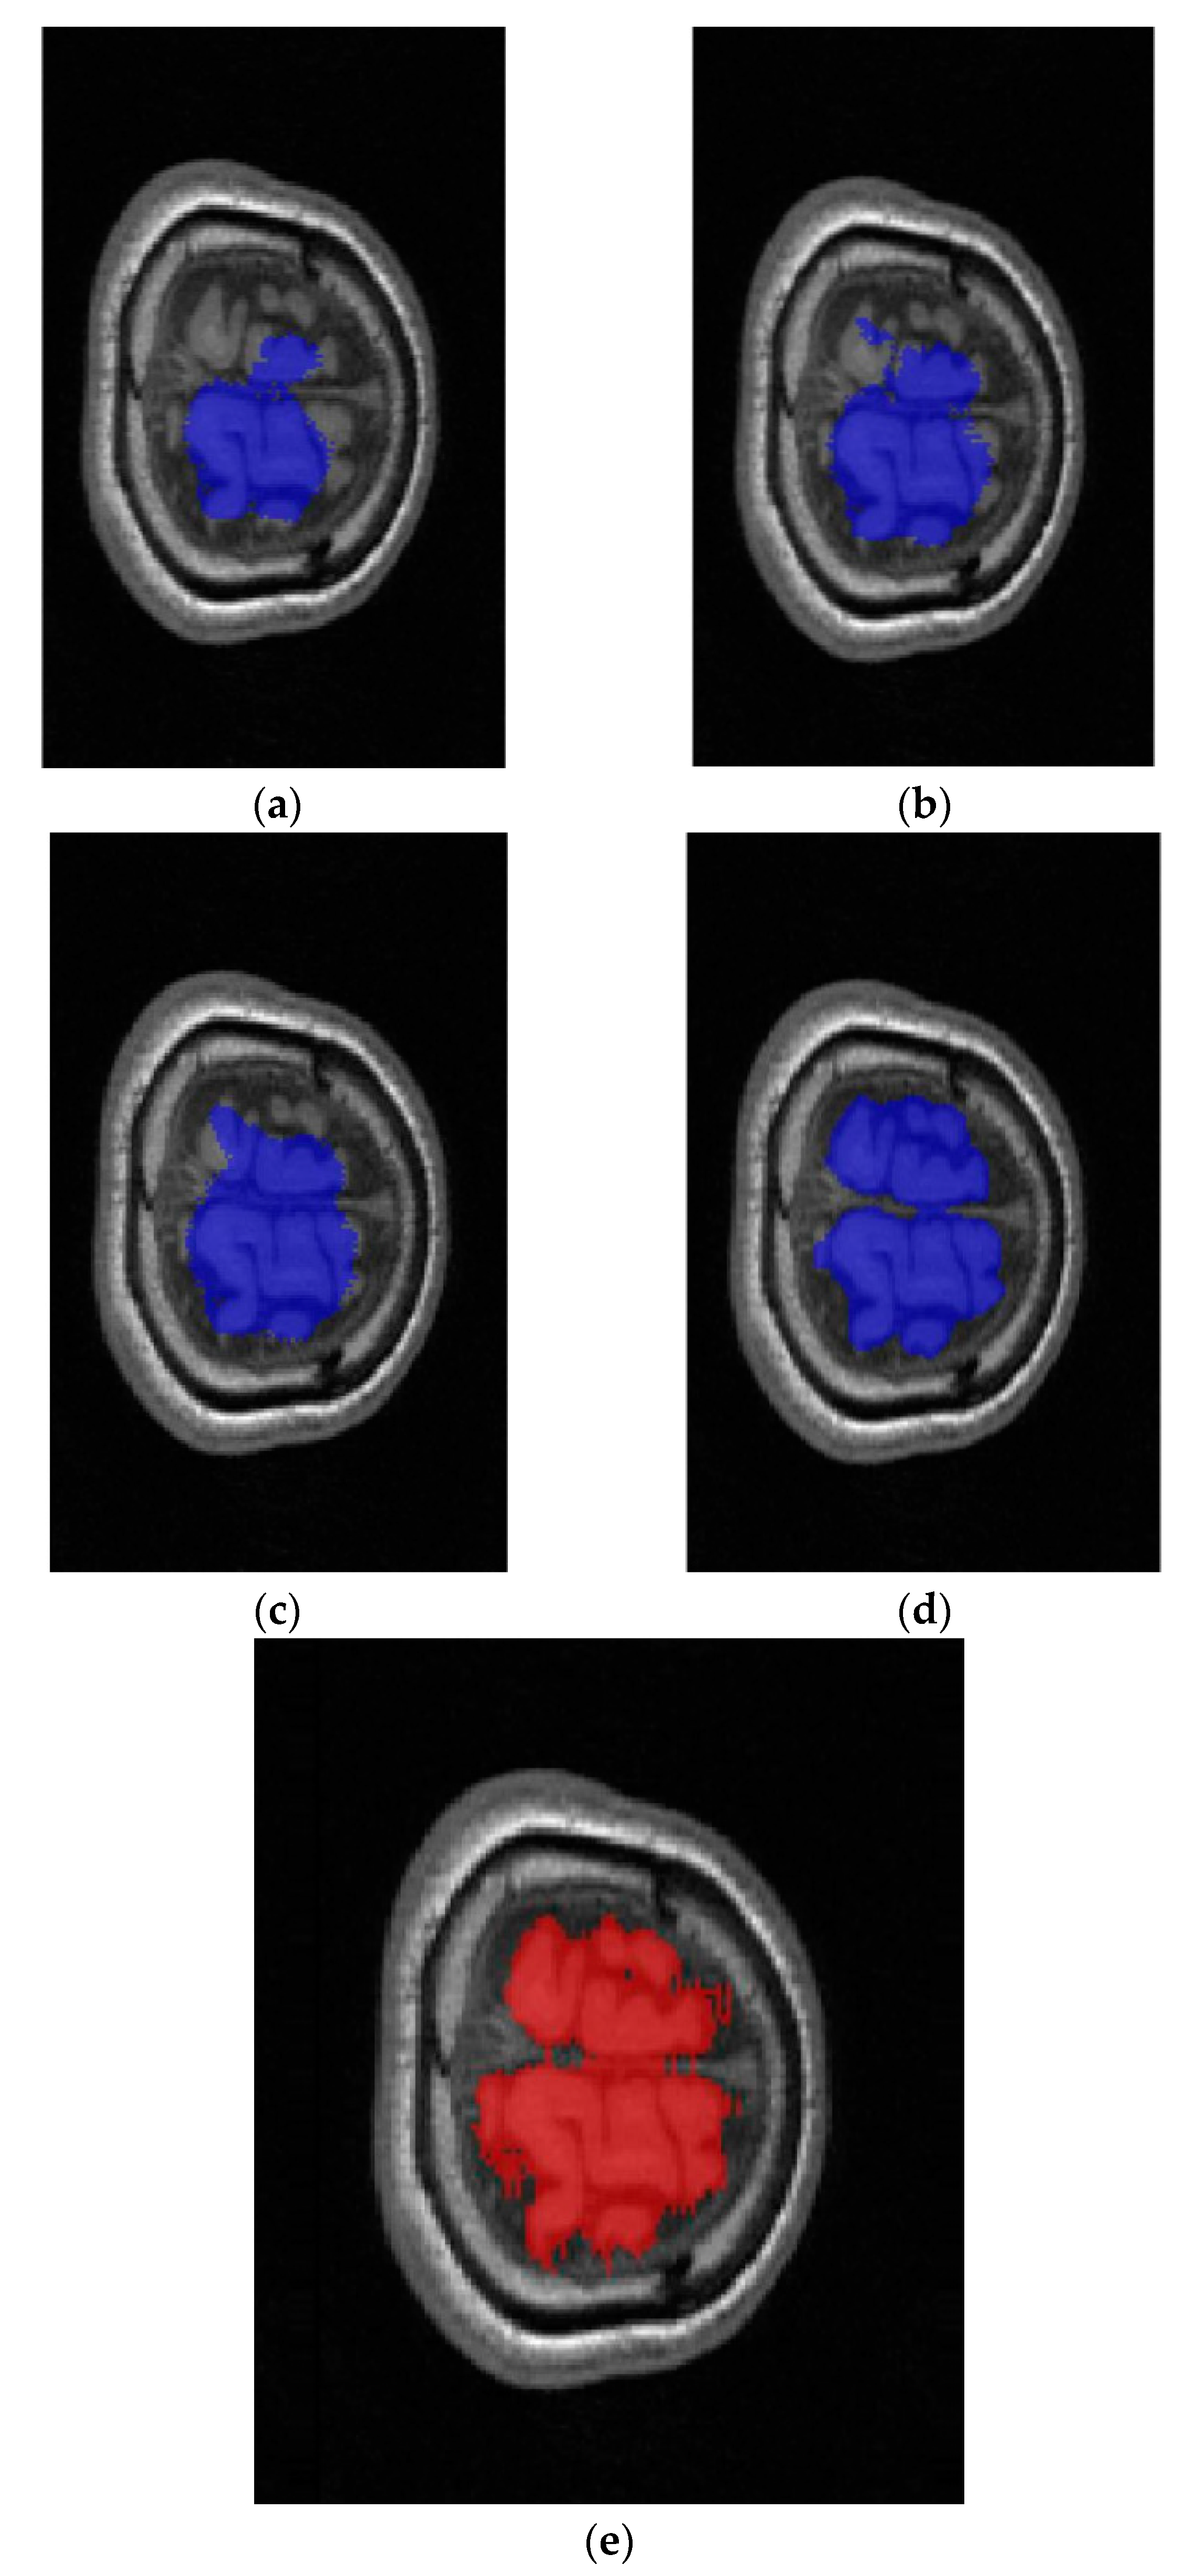

2.2. Full Image Information Mining with a K-Means Cluster Preprocessing

2.3. Hybrid-U-Net Framework

2.4. Dimensionality Reduction U-Net for 3D MRI Data